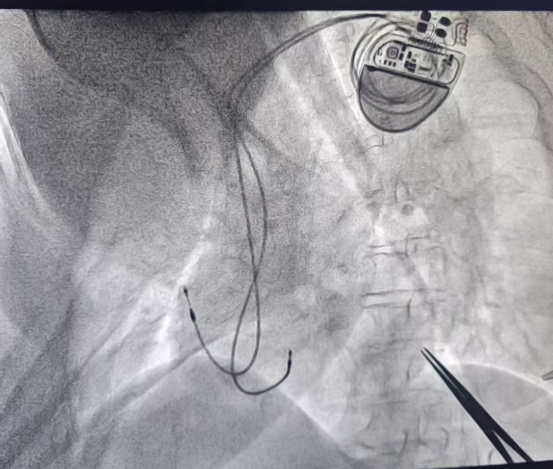

五一劳动节期间,泌阳县人民医院冠心病重症团队与省级专家协作,成功为两名严重心律失常患者实施心脏起搏器植入术,其中一位91岁高龄老人术后恢复良好。这场跨越年龄的生命守护战,不仅展现了现代医学的突破性进展,更让大众重新认识了心脏起搏器这项"救命技术"。

现代起搏器植入术通过锁骨下3-5cm切口,将电极导线经血管送入心脏,连接仅重20-30克的脉冲发生器。这台"智能节拍器"能24小时监测心电活动,在心脏偷停时立即发放电脉冲,就像为心脏配备专属"急救员"。手术全程局部麻醉,患者清醒状态下2小时即可完成,术后次日即可下床活动。起搏器锂电池寿命达8-12年,更换手术简便安全。